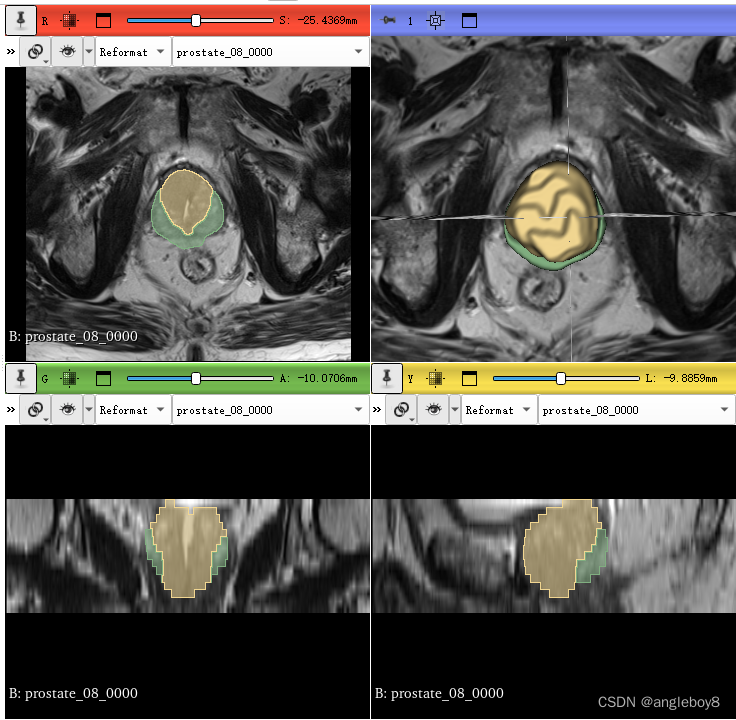

推理后得到标注结果:

现在已基本掌握了如何利用nnUNet以后模型进行推理,先会用再学如何利用自己的数据进行训练,之后重点讲如何自定义训练。这篇博客主要是为了解决nnUNet如何在win11环境中解决数据转换和数据预处理,以及如何模型推理。目前国内win11环境安装配置为此独一份,原创来之不易,点赞收藏,后期更精彩。